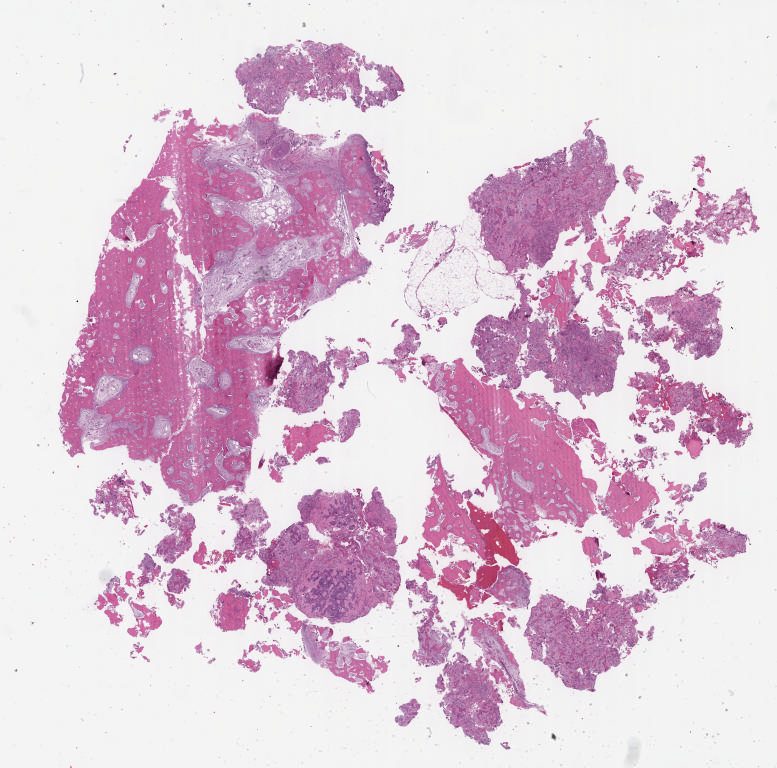

Case1.svs

87648

x

86606

@

40X